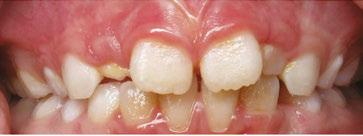

Delayed eruption of both deciduous and permanent teeth in certain special needs children, such as those with Down syndrome, are often seen. In these children, delays in the normal eruption pattern may be up to 2 years.5 Some children with Down syndrome retain their deciduous teeth until up to 15 years of age.5 This commonly leads to both malocclusion and overcrowding.6 These orthodontic issues very frequently lead to serious dental concerns which the dentist must be both aware of and take actions to mitigate their effects. Such actions can include the use of fluoride therapies and an increased amount of time spent educating both the patient and caregiver on oral hygiene techniques.

Special needs dental patients experience many obstacles to achieving ideal oral health. Some of these challenges include overcrowding, delayed eruption of teeth, and an increased incidence of dental caries. Homecare and oral hygiene are extremely important for everyone, but it is imperative for special needs patients that their oral hygiene and homecare are at a very high level. The importance of oral hygiene must be reinforced at every dental visit. Oral hygiene instructions must be regularly reviewed not only with the patient but, also with the patient’s caregiver. An electric toothbrush might be recommended for patients with manual dexterity difficulties. Home fluoride therapies also are recommended to combat their high incidence of dental decay. Also, working with an orthodontist may prove useful in order to correct overcrowding issues which can cause difficulty in keeping the teeth clean which can lead to dental decay.